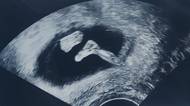

Hyperemesis gravidarum - komplikace nahánějící ženám strach z těhotenství

V dobách, kdy tak hořce pláčeme nad nízkou porodností a zbrojíme proti potratům, se doslova nabízí exkurz do slastí, jež leckteré těhotenství skýtá. Víte například, co je to hyperemesis gravidarum?